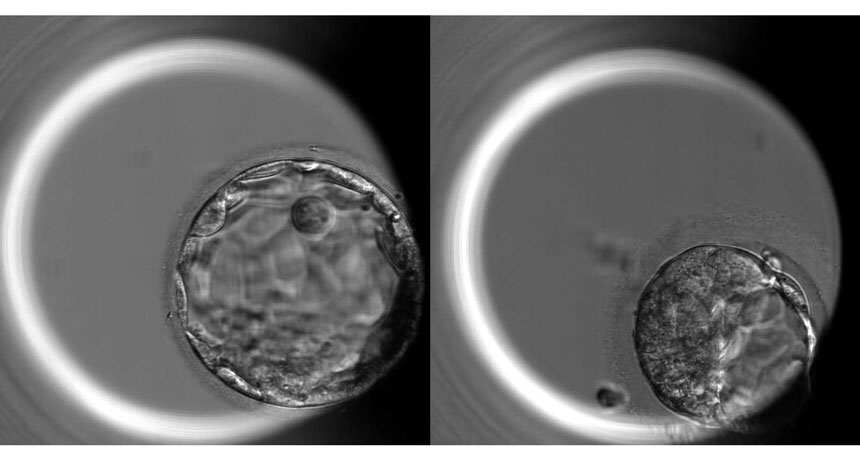

EMBRYO, INTERRUPTED  A 5-day-old human embryo is usually composed of about 200 cells in a hollow ball configuration called a blastocyst (left). Embryos edited to remove the OCT4 gene (right) fail to make normal blastocysts.

K. Niakan/Nature 2017